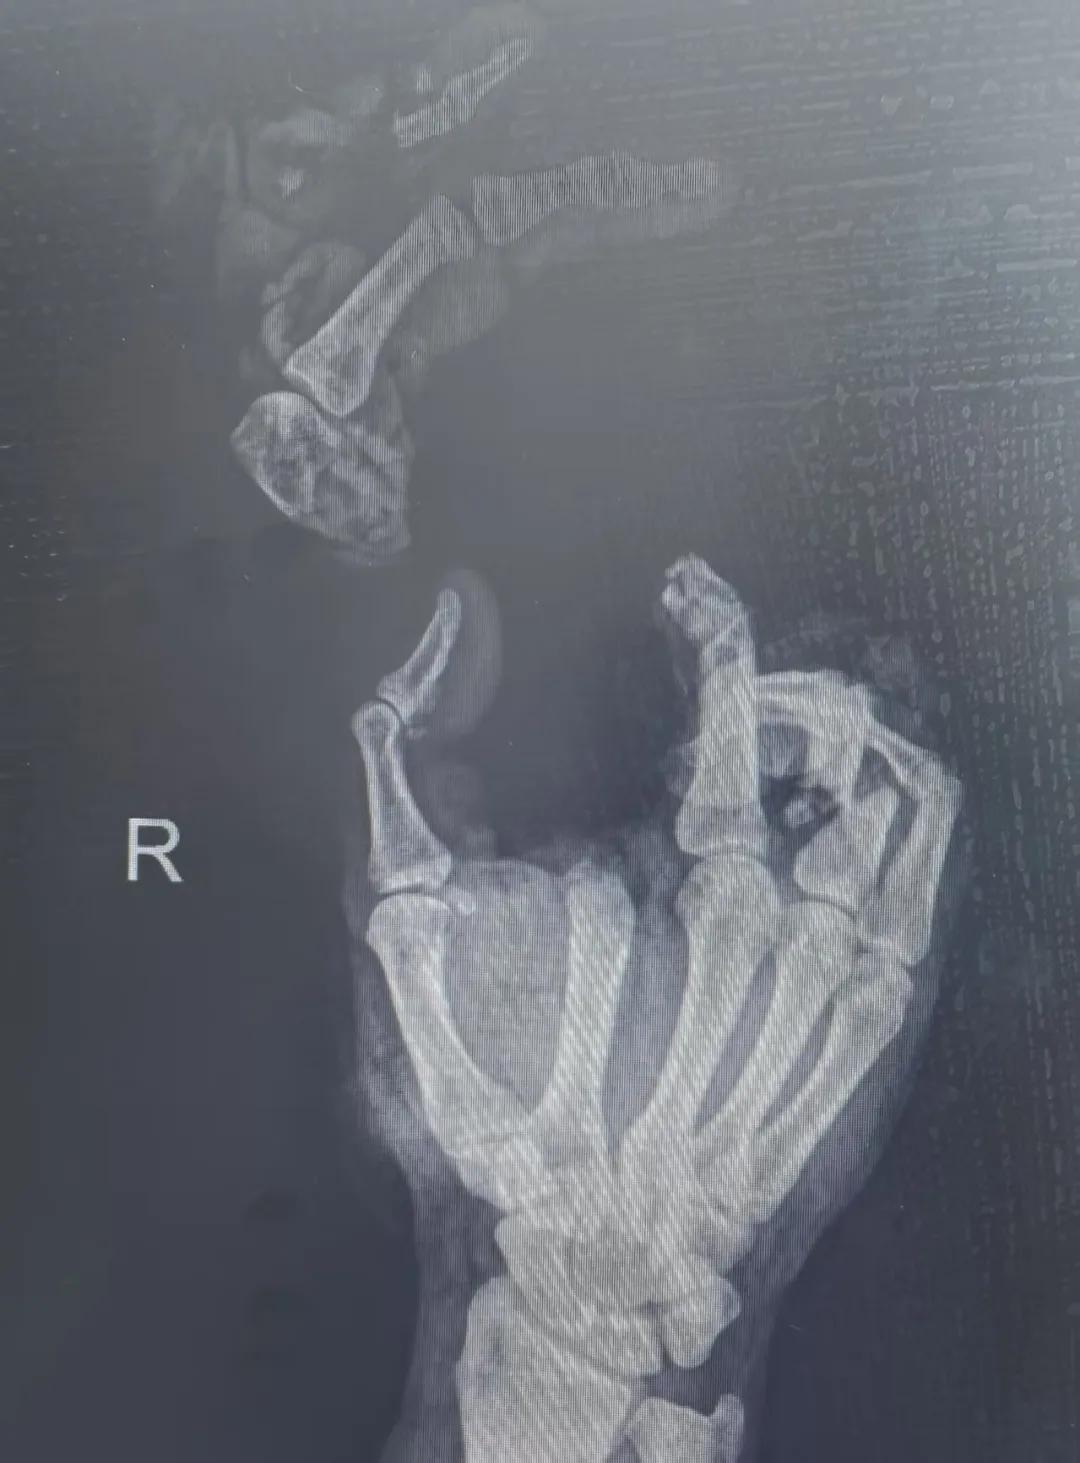

5月20日,市二院顯微外科燒傷整形科收治了3例因麥?zhǔn)毡晦r(nóng)機“咬傷”、農(nóng)具劃傷的患者。其中,56歲的劉某在收麥子時被打谷機皮帶絞傷右手,致手掌、食指、中指、環(huán)指嚴(yán)重毀損傷,骨、關(guān)節(jié)外露,因當(dāng)?shù)蒯t(yī)院無法治療,被家人緊急送往市二院顯微手足燒傷整形外科救治。“當(dāng)時整個右手血肉模糊,看上去都是爛的,我以為這個手是肯定保不住了。”患者家屬回憶當(dāng)時的場景仍然膽戰(zhàn)心驚。

患者入院后,經(jīng)X線檢查及創(chuàng)面檢查,醫(yī)生診斷為右手食指、中指及環(huán)指旋轉(zhuǎn)撕脫性離斷。接診的顯微手足燒傷整形外科醫(yī)護人員立即完善了各項術(shù)前準(zhǔn)備,并安排急診手術(shù)。因創(chuàng)面污染嚴(yán)重以及離斷肢體損傷程度較重,手術(shù)歷時近10小時。在沈衛(wèi)軍主任的帶領(lǐng)下,科室團隊成功為其進行了創(chuàng)面擴創(chuàng)、斷肢再植術(shù),術(shù)后患指血運良好,在進一步觀察治療中。